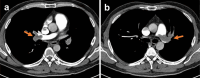

A 46-year-old Japanese man was referred to our hospital because of a marked increase in his eosinophil count (22,870/μL) and elevated liver enzyme levels. Computed tomography (CT) showed thrombi measuring approximately 8 cm in both femoral veins. A liver biopsy revealed eosinophilic infiltration, hepatocyte necrosis, fibrosis, and multiple thrombi. We suspected acute liver injury and deep vein thrombosis associated with hypereosinophilic syndrome and initiated steroids and heparin treatment. Four days after starting treatment, the patient experienced sudden chest pain and cardiopulmonary arrest. CT revealed bilateral pulmonary artery thrombosis, and despite administration of a tissue plasminogen activator, the patient died.